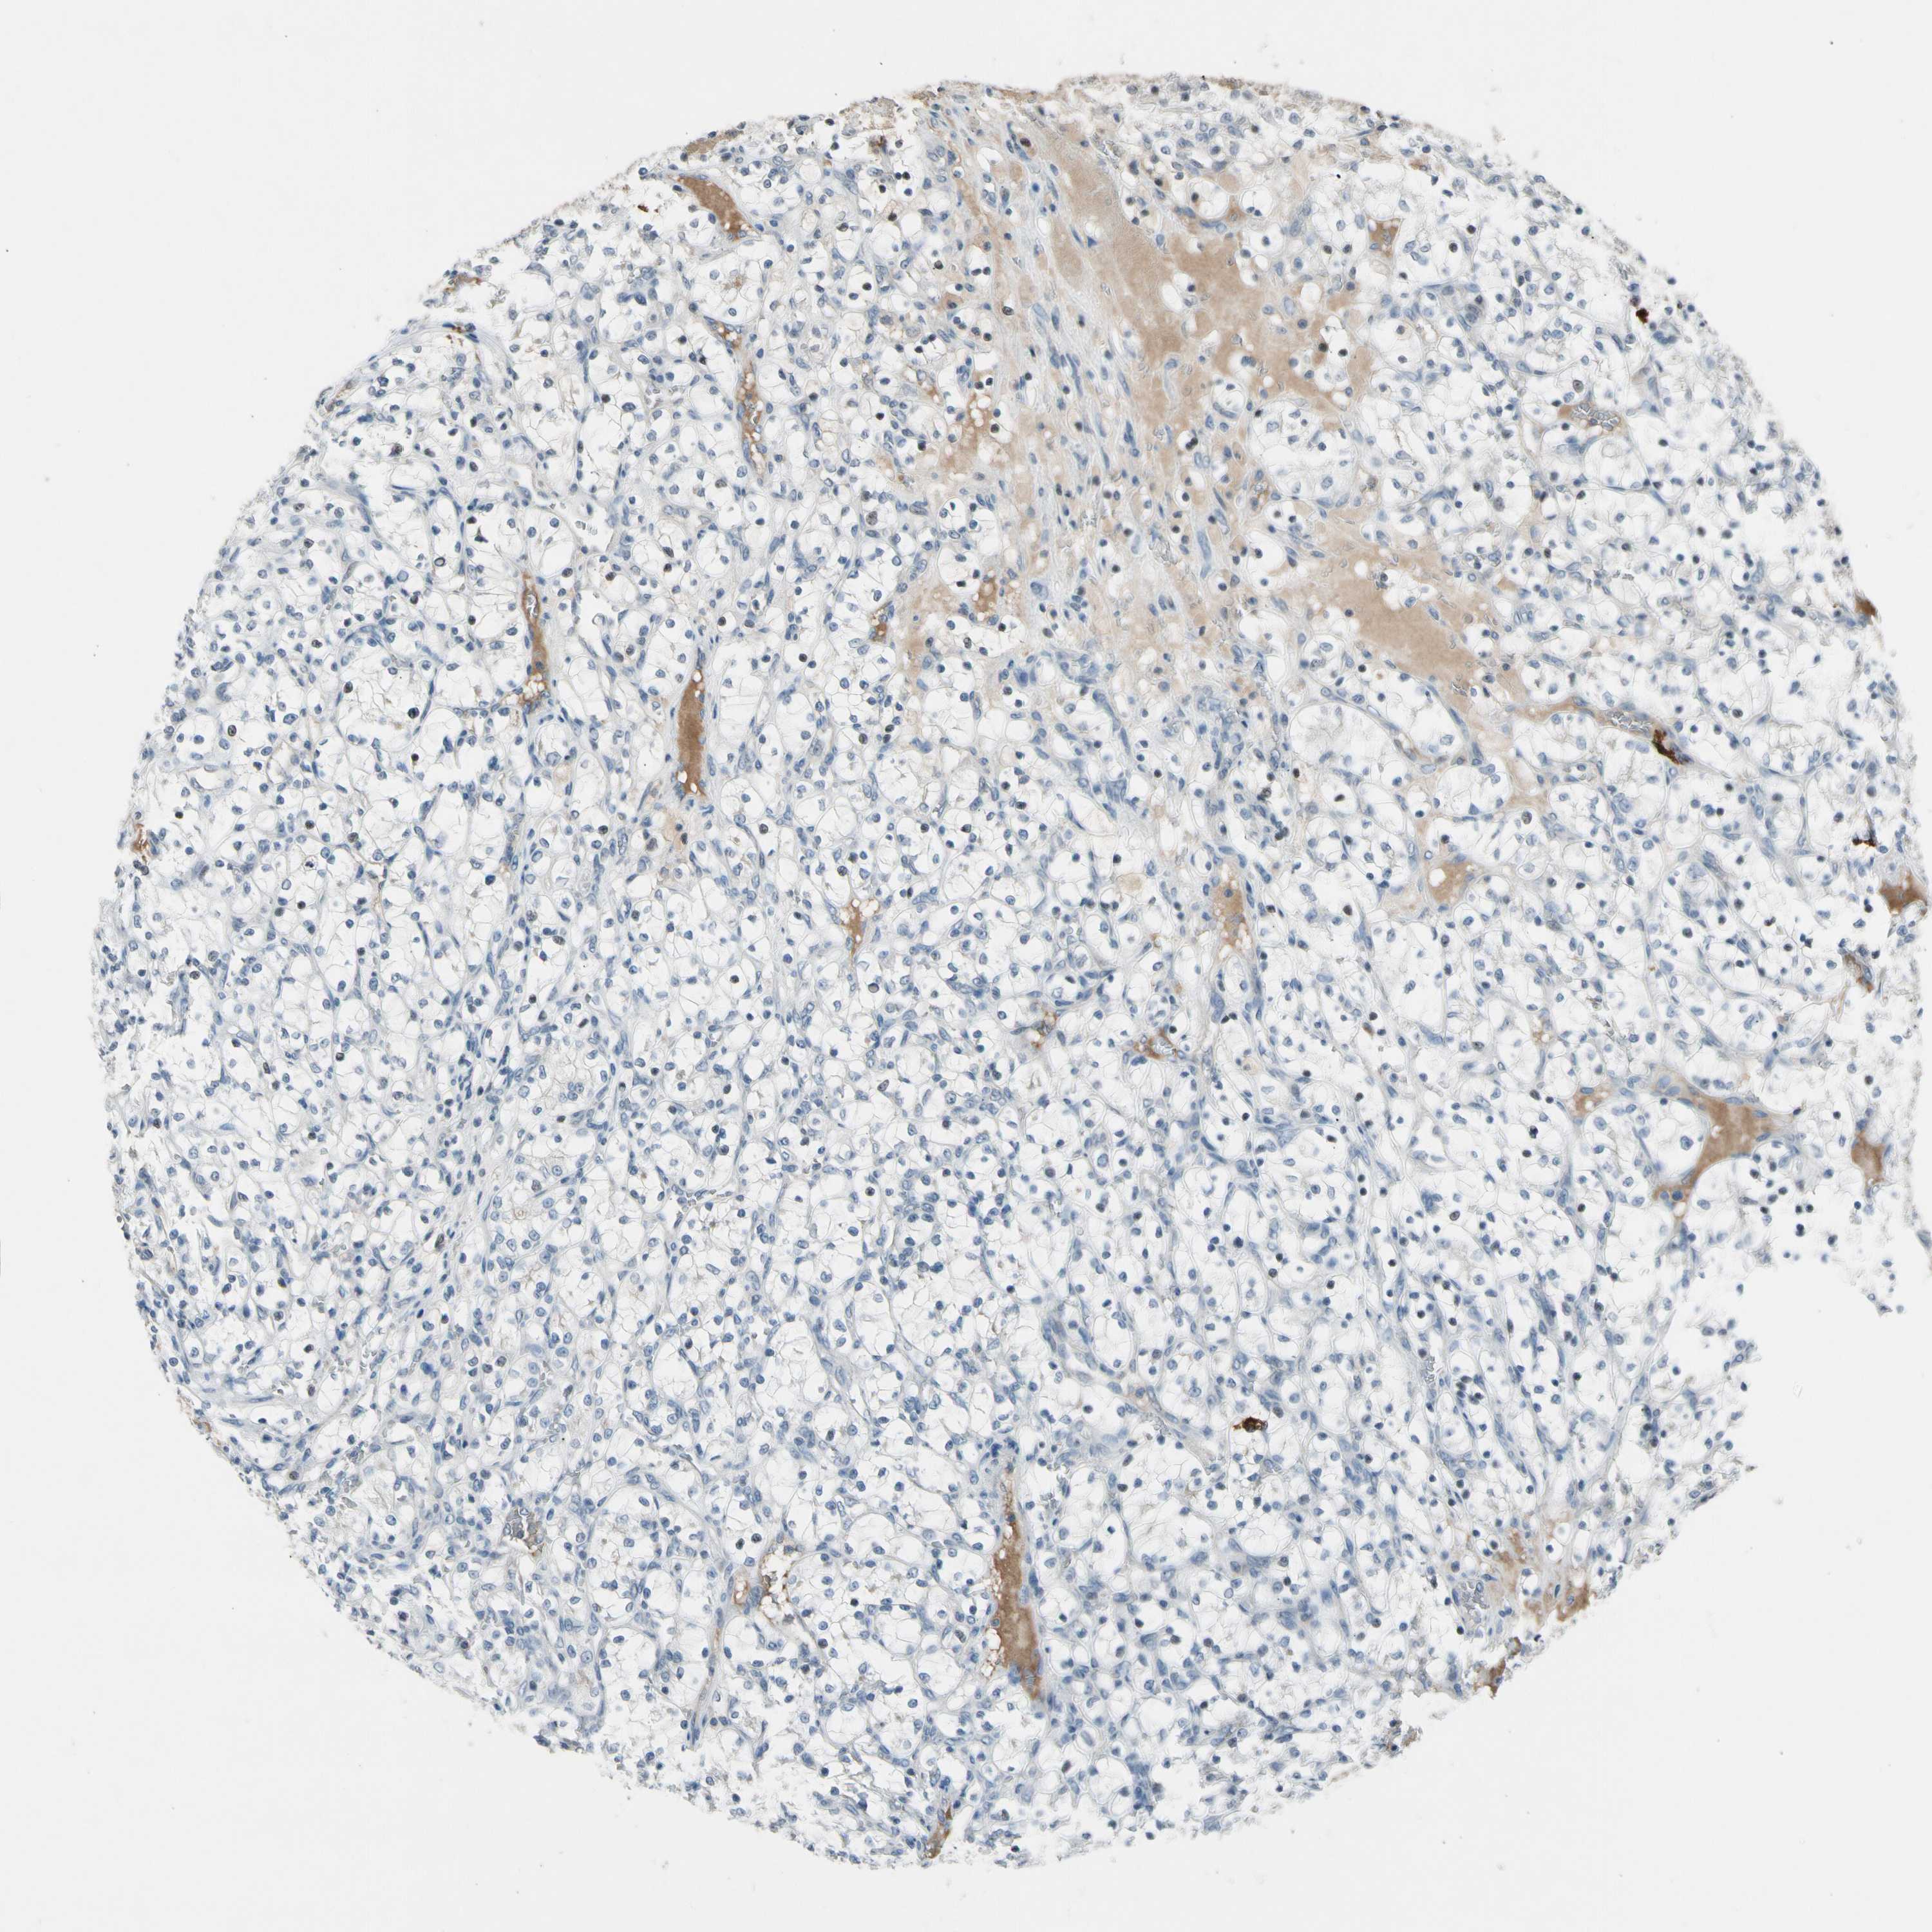

CANCER RENAL CANCER Show tissue menu